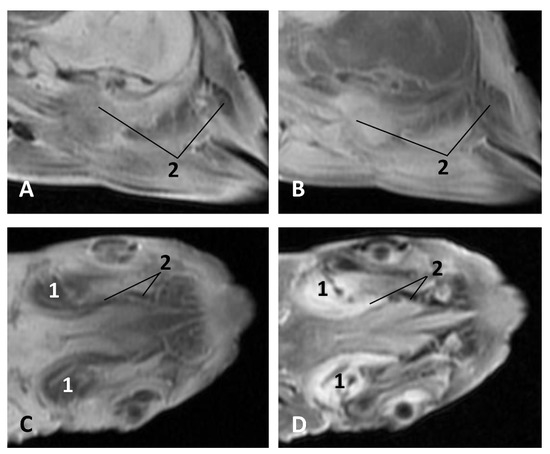

The MRI sagittal images show a pharyngeal cavity in a Globicephala melas fetus (gma1) and we could appreciate the oropharynx (fauces), the nasopharynx and the oesophageal vestibule hypointense in both T1 and T2 sequences(Figure 25A,B). Coronal T1 and T2 sequences show the piriform recess alongside the larynx (Figure 25C,D).

In MRI, we can appreciate, in early fetal stages, a bilateral structure within the laryngopharyngeal cavity, each named as a pharyngeal diverticulum of the auditory tube (PDAT). These are connected through the musculotubaric channel with the middle ear (temporal bone: petrous and tympanic part). In a young Delphinus delphis fetus (dde3), it appears in sagittal sections as a hyper/hypointense area seen caudal and rostrally, respectively (Figure 26A,B), and also in coronal sections (Figure 26C,D).

Figure 25. Images of the oral and pharyngeal cavity. MR sagittal and coronal images are oriented so that the rostral is to the right. (A) T1 SE sagittal, (B) T2 FrFSE sagittal, (C) T1 SE coronal and (D) T2 FrFSE coronal planes. 5 months, gma1. 1, Hard palate; 2, Tongue; 3, Oral cavity (closed); 4, Oropharynx: fauces; 5, Oropharynx: soft palate; 6, Laryngopharynx: left piriform recess; 7, Laryngopharynx: oesophageal vestibule; 8, Epiglottis cartilage; 9, Epiglottic vallecula; 10, Arytenoid cartilages; 11, Nasopharynx; 12, Larynx.

Figure 26. Images of the pharyngeal cavity. MR sagittal and coronal images are oriented so that the rostral is to the right. (A) T1 SE sagittal, (B) T2 FrFSE sagittal, (C) T1 SE coronal and (D) T2 FrFSE coronal planes. 4 months, dde3. 1, Inner and middle ear; 2, Pharyngeal diverticulum of the auditory tube.